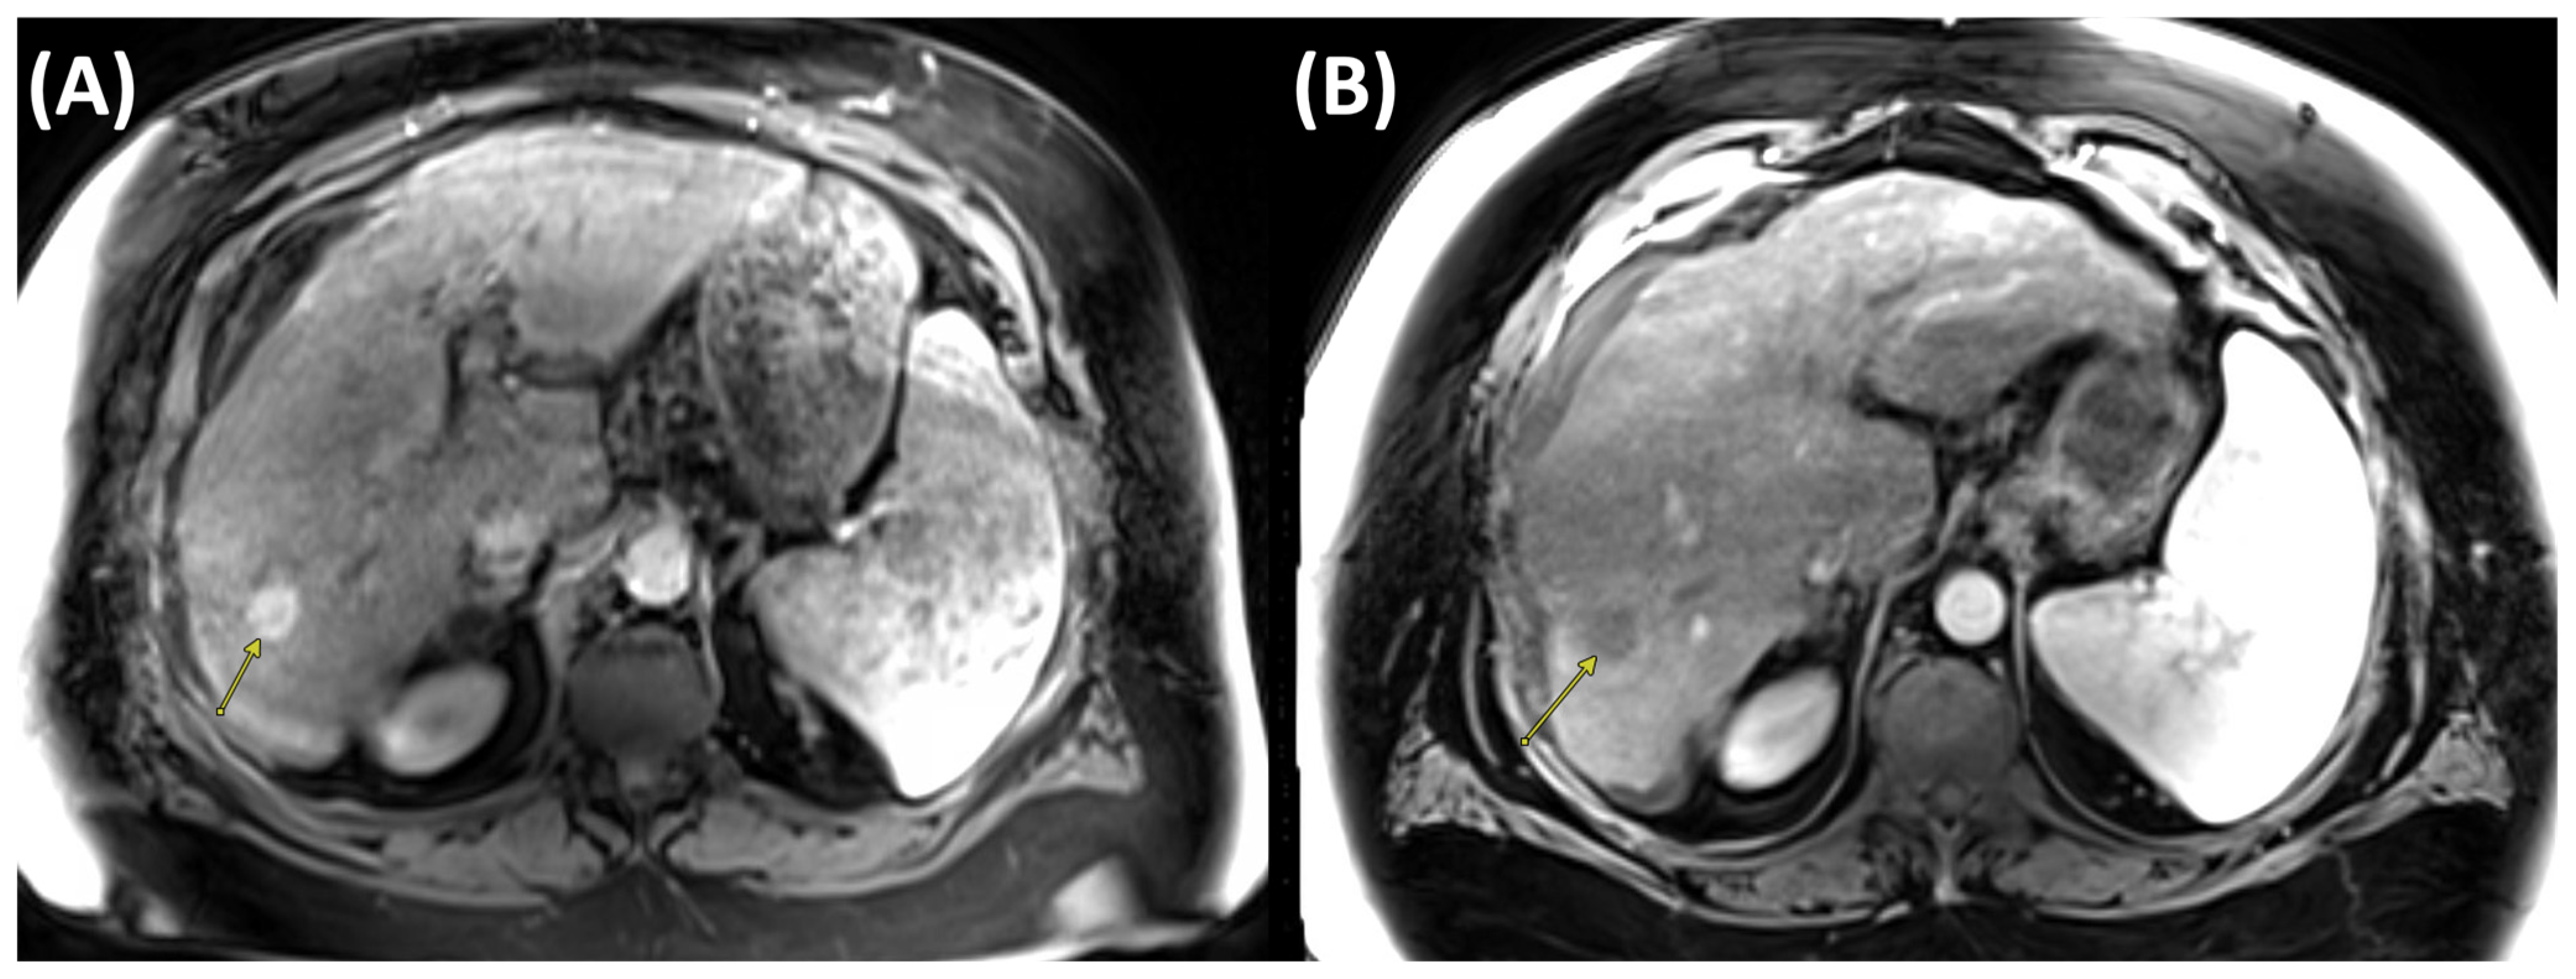

2.1. Radiofrequency Ablation (RFA)